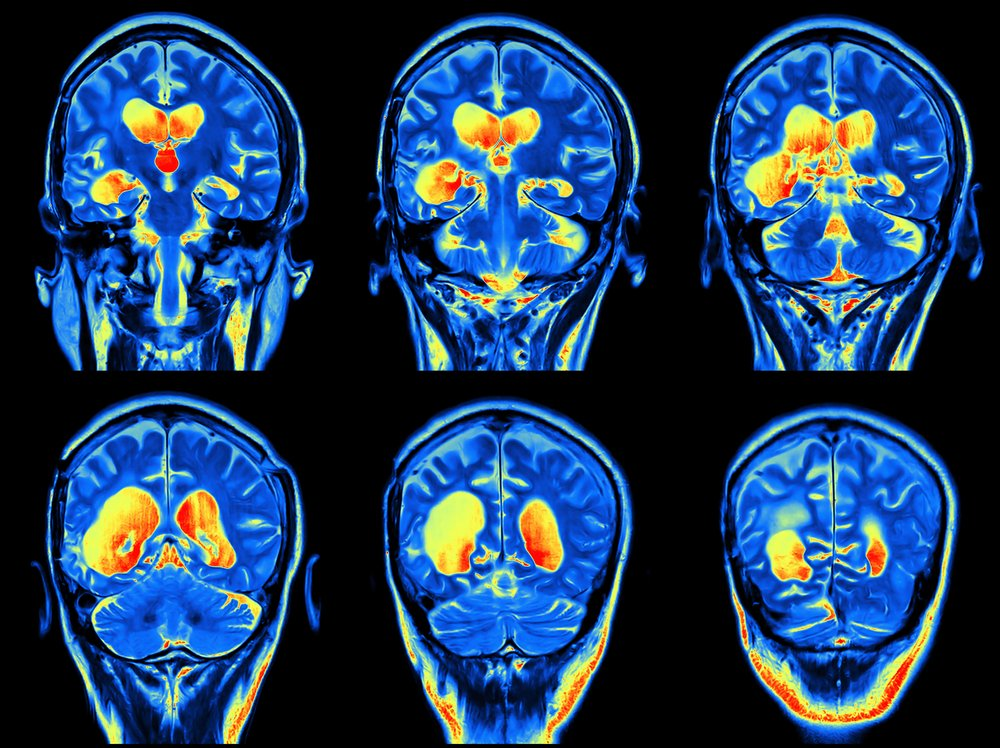

Contrast MRI एक advanced imaging test है जिसमें MRI scan के दौरान contrast dye (Gadolinium) का उपयोग किया जाता है।

👉 यह dye शरीर के अंदर जाकर tissues और blood vessels को ज्यादा clear और detailed बनाती है।

इससे doctors को accurate diagnosis करने में मदद मिलती है।

1. Better Image Quality

• Detailed images मिलती हैं

• Small lesions भी detect होते हैं

2. Accurate Diagnosis

• Tumor और infection clearly दिखाई देते हैं